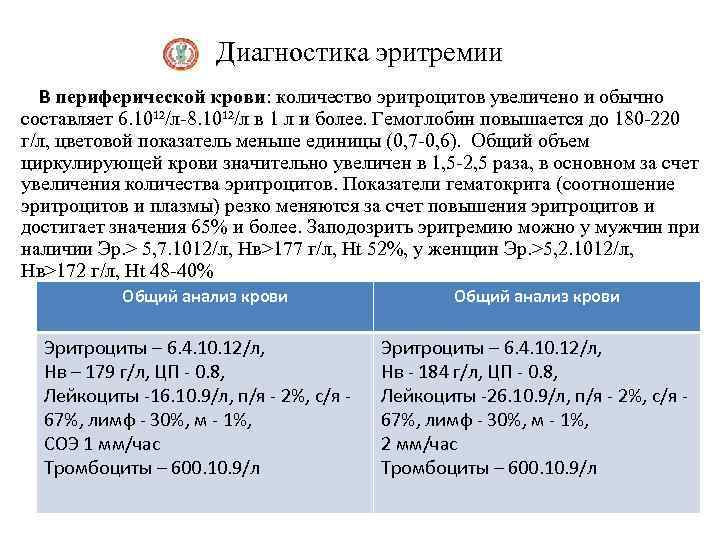

Диагностика эритремии В периферической крови: количество эритроцитов увеличено и обычно составляет 6. 10¹²/л-8. 10¹²/л в 1 л и более. Гемоглобин повышается до 180 -220 г/л, цветовой показатель меньше единицы (0, 7 -0, 6). Общий объем циркулирующей крови значительно увеличен в 1, 5 -2, 5 раза, в основном за счет увеличения количества эритроцитов. Показатели гематокрита (соотношение эритроцитов и плазмы) резко меняются за счет повышения эритроцитов и достигает значения 65% и более. Заподозрить эритремию можно у мужчин при наличии Эр. > 5, 7. 1012/л, Нв>177 г/л, Ht 52%, у женщин Эр. >5, 2. 1012/л, Нв>172 г/л, Ht 48 -40% Общий анализ крови Эритроциты – 6. 4. 10. 12/л, Нв – 179 г/л, ЦП - 0. 8, Лейкоциты -16. 10. 9/л, п/я - 2%, с/я - 67%, лимф - 30%, м - 1%, СОЭ 1 мм/час Тромбоциты – 600. 10. 9/л Эритроциты – 6. 4. 10. 12/л, Нв - 184 г/л, ЦП - 0. 8, Лейкоциты -26. 10. 9/л, п/я - 2%, с/я - 67%, лимф - 30%, м - 1%, 2 мм/час Тромбоциты – 600. 10. 9/л